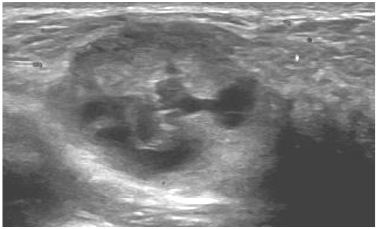

Paciente puérpera com 33 anos, informa que há duas semanas, durante amamentação, palpou um nódulo na mama direita.

O achado encontrado no exame de imagem classifica-se como: